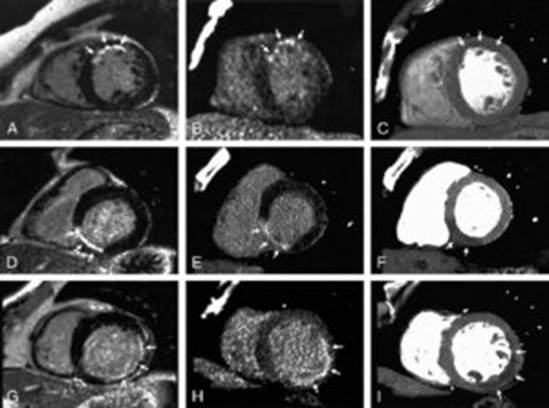

Мультиспиральная компьютерная томография (МСКТ или КТ) и магнитно-резонансная томография (МРТ) на сегодняшний день — ключевые методы неинвазивной диагностики заболеваний сердечно-сосудистой системы. Эти виды исследований с высокой точностью позволяют получить данные о состоянии тканей, органов и крупных кровеносных сосудов, а также установить диагноз, спрогнозировать дальнейшее развитие заболевания и разработать эффективную схему лечения. Каждый из них решает определенные задачи.

КТ сердца или МСКТ коронарных артерий обычно выполняется для получения знаний о сердечной или коронарной анатомии коронарных артерий, для обнаружения или диагностики ишемической болезни сердца (ИБС), для оценки проходимости шунтирования коронарных артерий или имплантированных коронарных стентов или для оценки объема и сердечной функции (включая фракцию выброса). Это метод скрининговой диагностики начальных признаков атеросклероза коронарных артерий, а также для отслеживания динамики заболевания и оценки эффективности проводимого лечения.

МРТ сердца при грамотном и своевременном подходе позволяет существенно облегчить диагностику, повысить шансы пациента на скорейшее выздоровление.